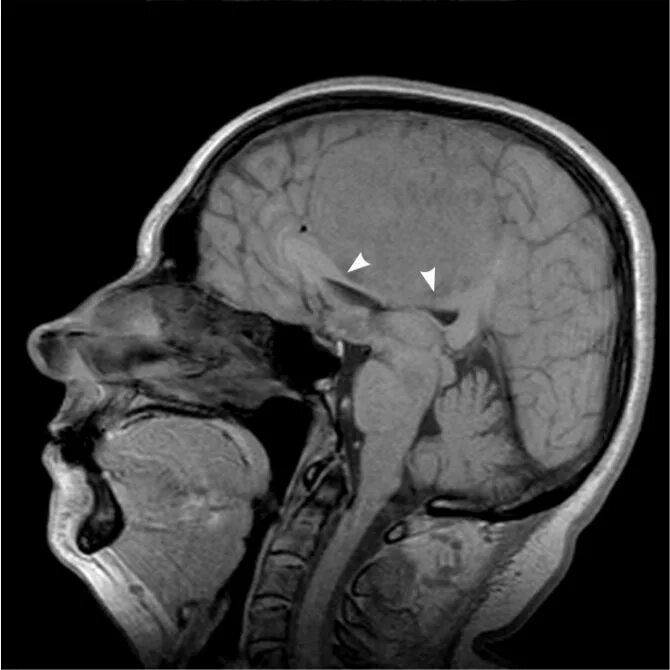

Отек головного мозга мрт